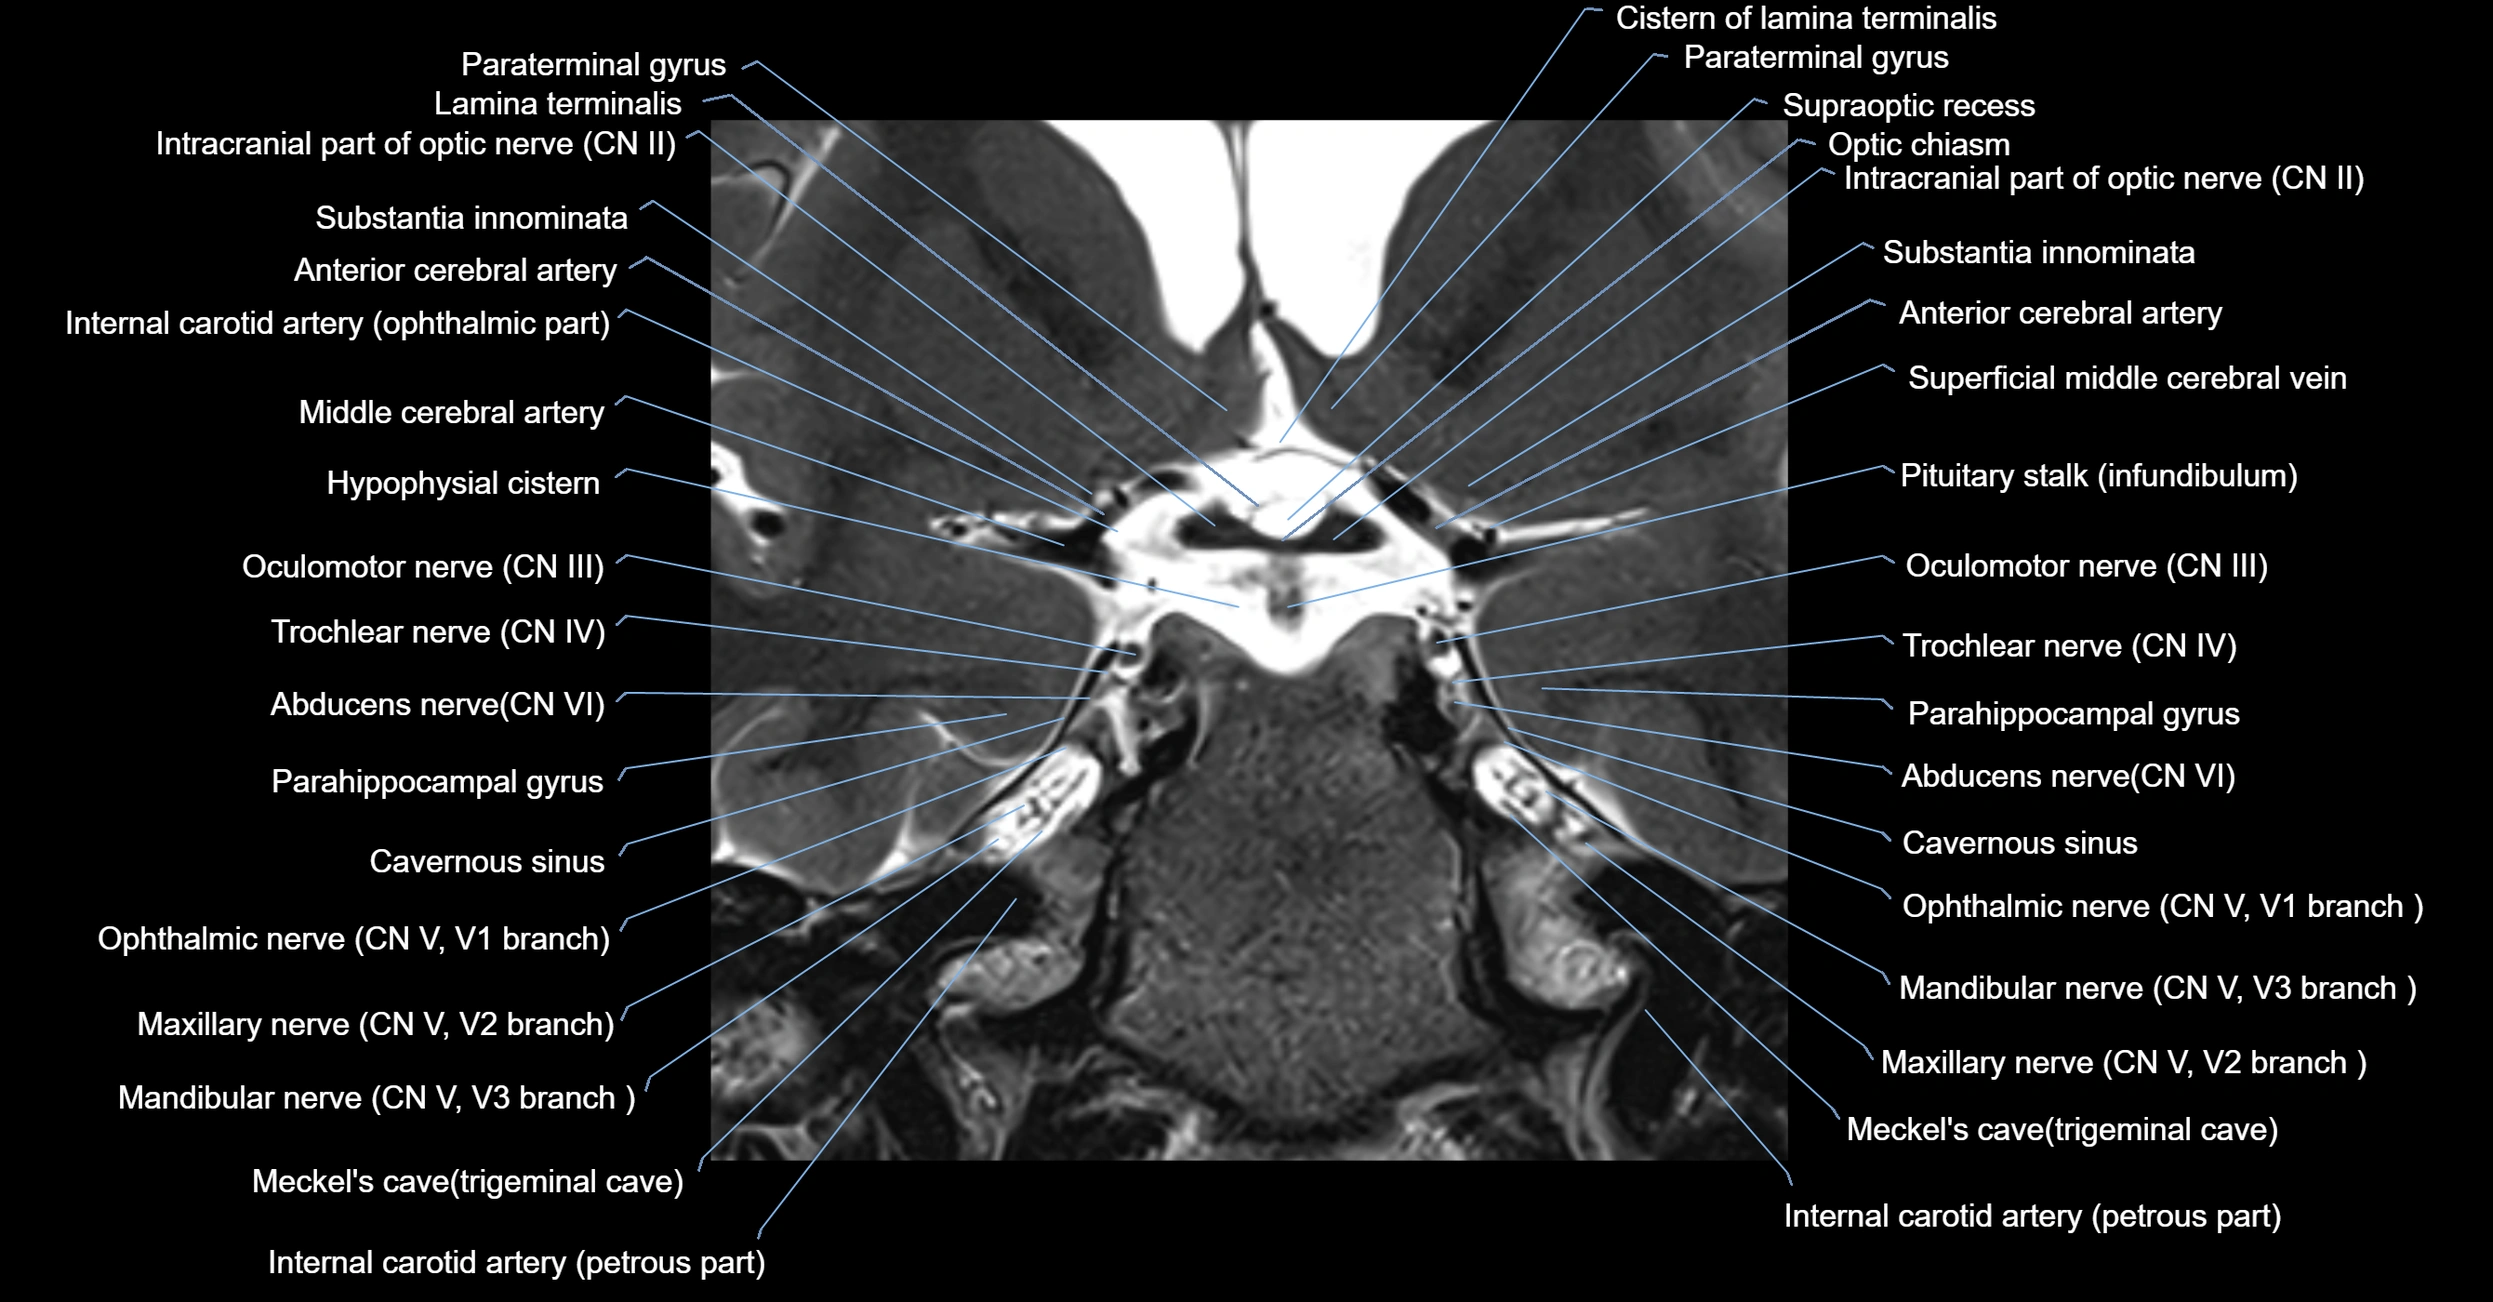

MRI images